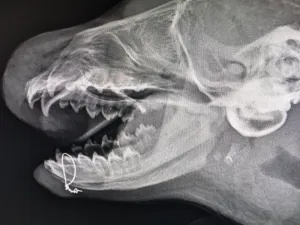

Ook een andere zeehond maakt het inmiddels weer goed. Dit kleine beestje heeft nog geen naam, maar werd binnen gebracht met een gebroken kaak. “De zeehond had een symphysis breuk, dat wil zeggen dat er een breuk is van het bot helemaal vooraan in de onderkaak,” legt dierenarts Machteld uit. “De operatie was nodig om het bot weer mooi aan elkaar te laten groeien.”

Op de onderstaande röntgenfoto is te zien hoe de kaak aan elkaar is gezet met een soort beugeltje. Het jonge zeehondje kan alweer zelf eten en het gaat hartstikke goed met hem.